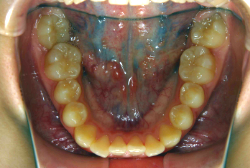

急速拡大装置を1日1回装置の中央にある拡大ネジを、ご自身で回して頂くことで25日間くらいかけて、6mmほど拡大しました。拡大後は、上顎の前歯の隙間が広がっていることがお分かりいただけると思うのですが、土台の骨ごと広がるのでこのような隙間ができます。その後1年半くらいマルチブラケット装置を使用して、全体の修正を行いました。